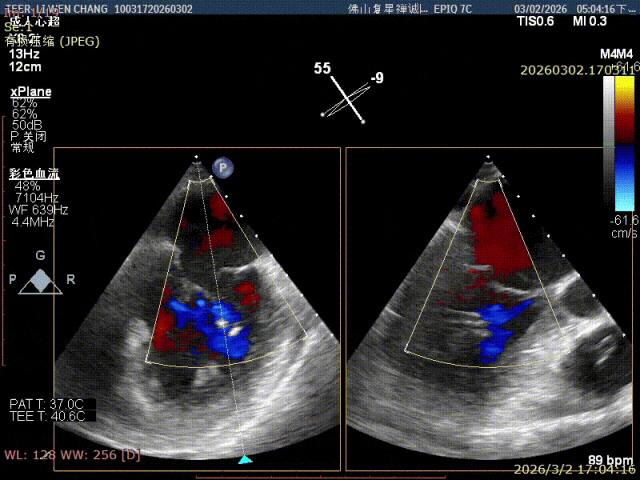

术前影像

X-plane1区 反流重度